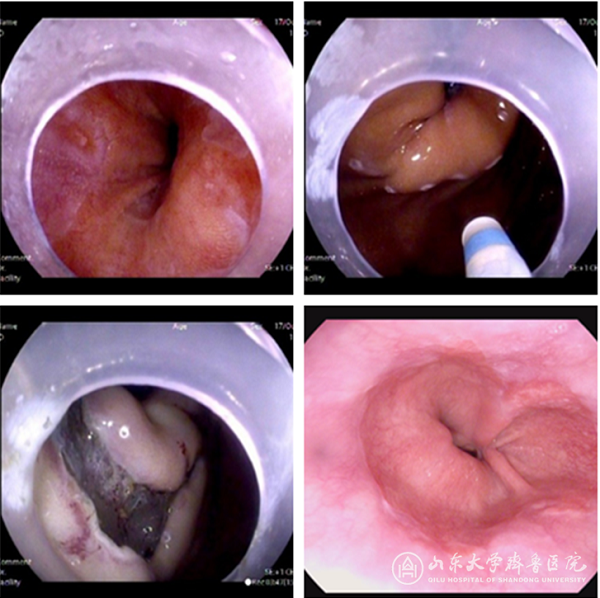

患者男性,65岁,饮食后上腹痛、反酸、烧心、夜间呛咳、胸骨后不适7年余;胃镜检查见食管下段纵行糜烂带,提示反流性食管炎;患者长期应用质子泵抑制剂治疗,效果欠佳,且上述不适症状和长期服药的现状使其精神焦虑,严重影响了其生活质量。与患者及家属充分沟通后决定行内镜抗反流贲门黏膜瓣成形术治疗,手术于2018年10月17日在李延青副院长指导下由卢雪峰主任医师顺利完成。首先于齿状线下方约5cm处大弯侧、前壁、后壁下方给予环3/4周标记,然后黏膜下注射,切开黏膜,向贲门侧行黏膜下剥离至贲门环肌,游离黏膜于齿状线下方呈瓣样收缩,最后对创面进行止血后退镜。术后给予禁饮食、营养支持、抑酸、预防感染等治疗。2天后嘱患者进流质饮食,无腹痛、反酸、烧心等不适。1.5月后复查胃镜,见创面愈合良好,贲门收缩功能明显改善,食管下段糜烂带消失,翻转镜身观察见瘢痕收缩及抗反流瓣抗反流效果好。

左上图:治疗前见贲门口松弛、图左上方见纵行糜烂带 右上图:于齿状线下方环3/4周标记

左下图:向贲门侧行黏膜下剥离,形成抗反流黏膜瓣 右下图:术后1.5月复查,见贲门口较术前收紧、糜烂带消失